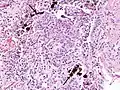

Extensive fibrosis of pleura and lung parenchyma.

The arrow points to an uncoated segment of asbestos fiber in this ferruginous body.

The black arrows point to ferrugionous bodies that are located at the periphery of a focus of non-small cell lung carcinoma, NOS.